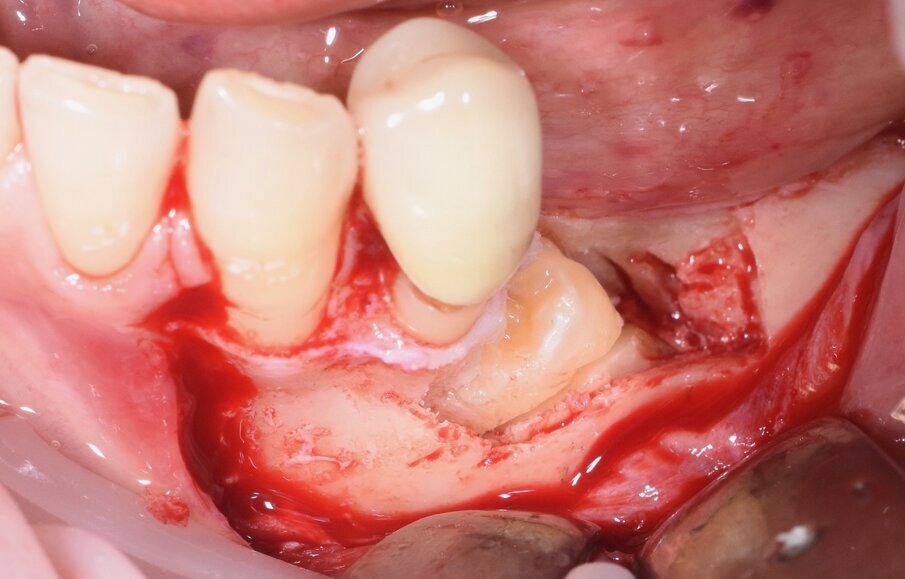

Considerata la necessità di eseguire un riabilitazione implantoprotesica della sede edentula si è resa necessaria l’avulsione dell’elemento incluso con tecnica piezoelettrica che ci ha permesso di ridurre al minimo l’osteotomia e preservare l’integrità del nervo la cui emergenza si trovava esattamente in corrispondenza della corona del 3.5 (Figg. 3-9).

Fig. 7 - Rimozione del tassello osseo e visione della corona del 3.5.

Fig. 8 - Odontotomia eseguita con inserto piezolettrico.